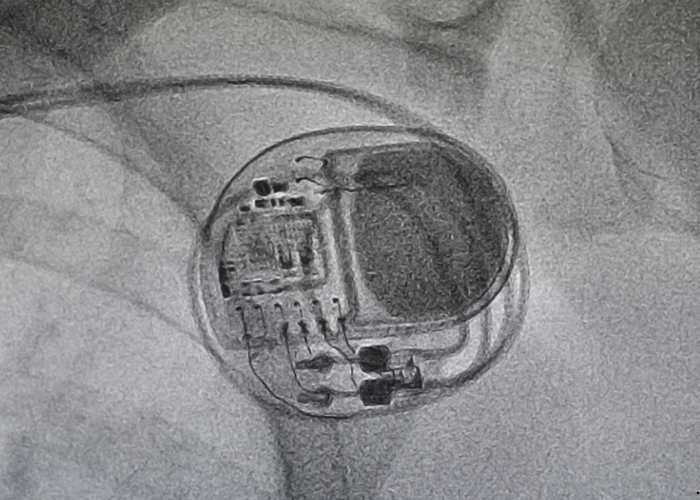

A permanent pacemaker is implanted in patients whose hearts beat too slowly or irregularly, causing fatigue, dizziness, or fainting. It sends electrical signals to maintain a steady heart rate, especially in cases of bradycardia or heart block. An ICD is recommended for patients at high risk of life-threatening arrhythmias or sudden cardiac arrest. It continuously monitors heart rhythm and delivers a shock if a dangerous rhythm is detected. These devices are implanted just below the collarbone under local anesthesia. Leads (wires) are threaded through veins into the heart to deliver electrical impulses. The procedure usually takes 1–2 hours, and most patients return home the next day.